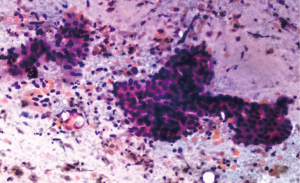

A 62-year-old female presented to gynecology out-patient department (OPD) in March 2025 with complaints of episodic bleeding per vaginum for 6 months (symptoms began around September 2024). It was insidious in onset, gradually progressive and associated with dull pelvic pain and foul-smelling discharge per vaginum. A history of occasional epigastric discomfort with significant weight loss was also elicited. No relevant medical, surgical, family, or personal history was noted. Pelvic examination revealed a 2 cm × 2 cm friable polypoidal growth over the cervical os without parametrial/rectal mucosal involvement. Magnetic resonance imaging (MRI) of the abdomen and pelvis demonstrated an ill-defined soft tissue lesion in the neck & body of pancreas measuring 3.2 cm × 4.2 cm × 3.2 cm, completely encasing the portal, splenic and superior mesenteric veins. Another soft tissue lesion of 2 cm × 2.2 cm × 3 cm was seen in cervical and lower uterine segment without any parametrial extension (Figure 1). Whole body positron emission tomography-computed tomography (PET-CT) scan showed high metabolic activity in the pancreatic and cervical lesions, with no other metabolically active focus elsewhere in the body (Figure 2). Serum carcinoembryonic antigen (CEA) was 22 ng/mL (normal: <3 ng/mL) and carbohydrate antigen 19-9 (CA19-9) was 1,532 U/mL (normal: <35 U/mL). Hemogram and other biochemistry parameters were within normal limits.Endoscopic ultrasound-guided fine needle aspiration cytology from pancreatic mass showed adenocarcinoma with mucinous differentiation (Figure 3). Punch biopsy from cervix was suggestive of adenocarcinoma.

IHC was performed on the cervical biopsy for further characterization. The tumor cells were found to be positive for cytokeratin 7 (CK7), caudal type homeobox 2 (CDX2) and CA19-9, while they were negative for p16, p63 and paired box protein-8 (PAX-8) (Figures 4-7). Based on imaging, histopathology and IHC, the disease was staged as cT4N0M1 (stage IV) according to the American Joint Committee on Cancer (AJCC) 8th edition for pancreatic adenocarcinoma.